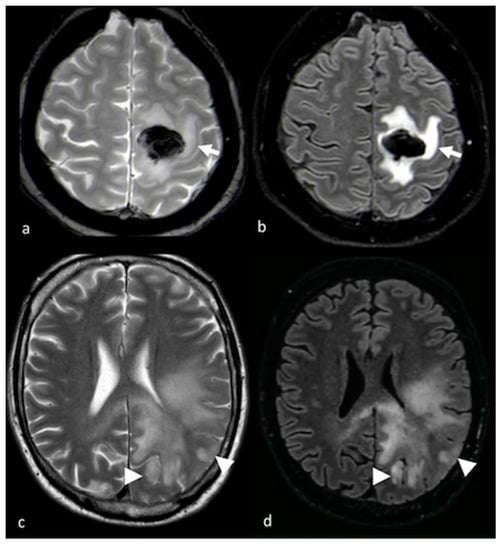

- Tang, Y.M.; Ngai, S.; Stuckey, S. The solitary enhancing cerebral lesion: Can FLAIR aid the differentiation between glioma and metastasis? AJNR Am. J. Neuroradiol. 2006, 27, 609–611. [Google Scholar] [PubMed]

- Wang, P.; Shi, Y.H.; Li, J.Y.; Zhang, C.Z. Differentiating Glioblastoma from Primary Central Nervous System Lymphoma: The Value of Shaping and Nonenhancing Peritumoral Hyperintense Gyral Lesion on FLAIR Imaging. World Neurosurg. 2021, 149, e696–e704. [Google Scholar] [CrossRef]